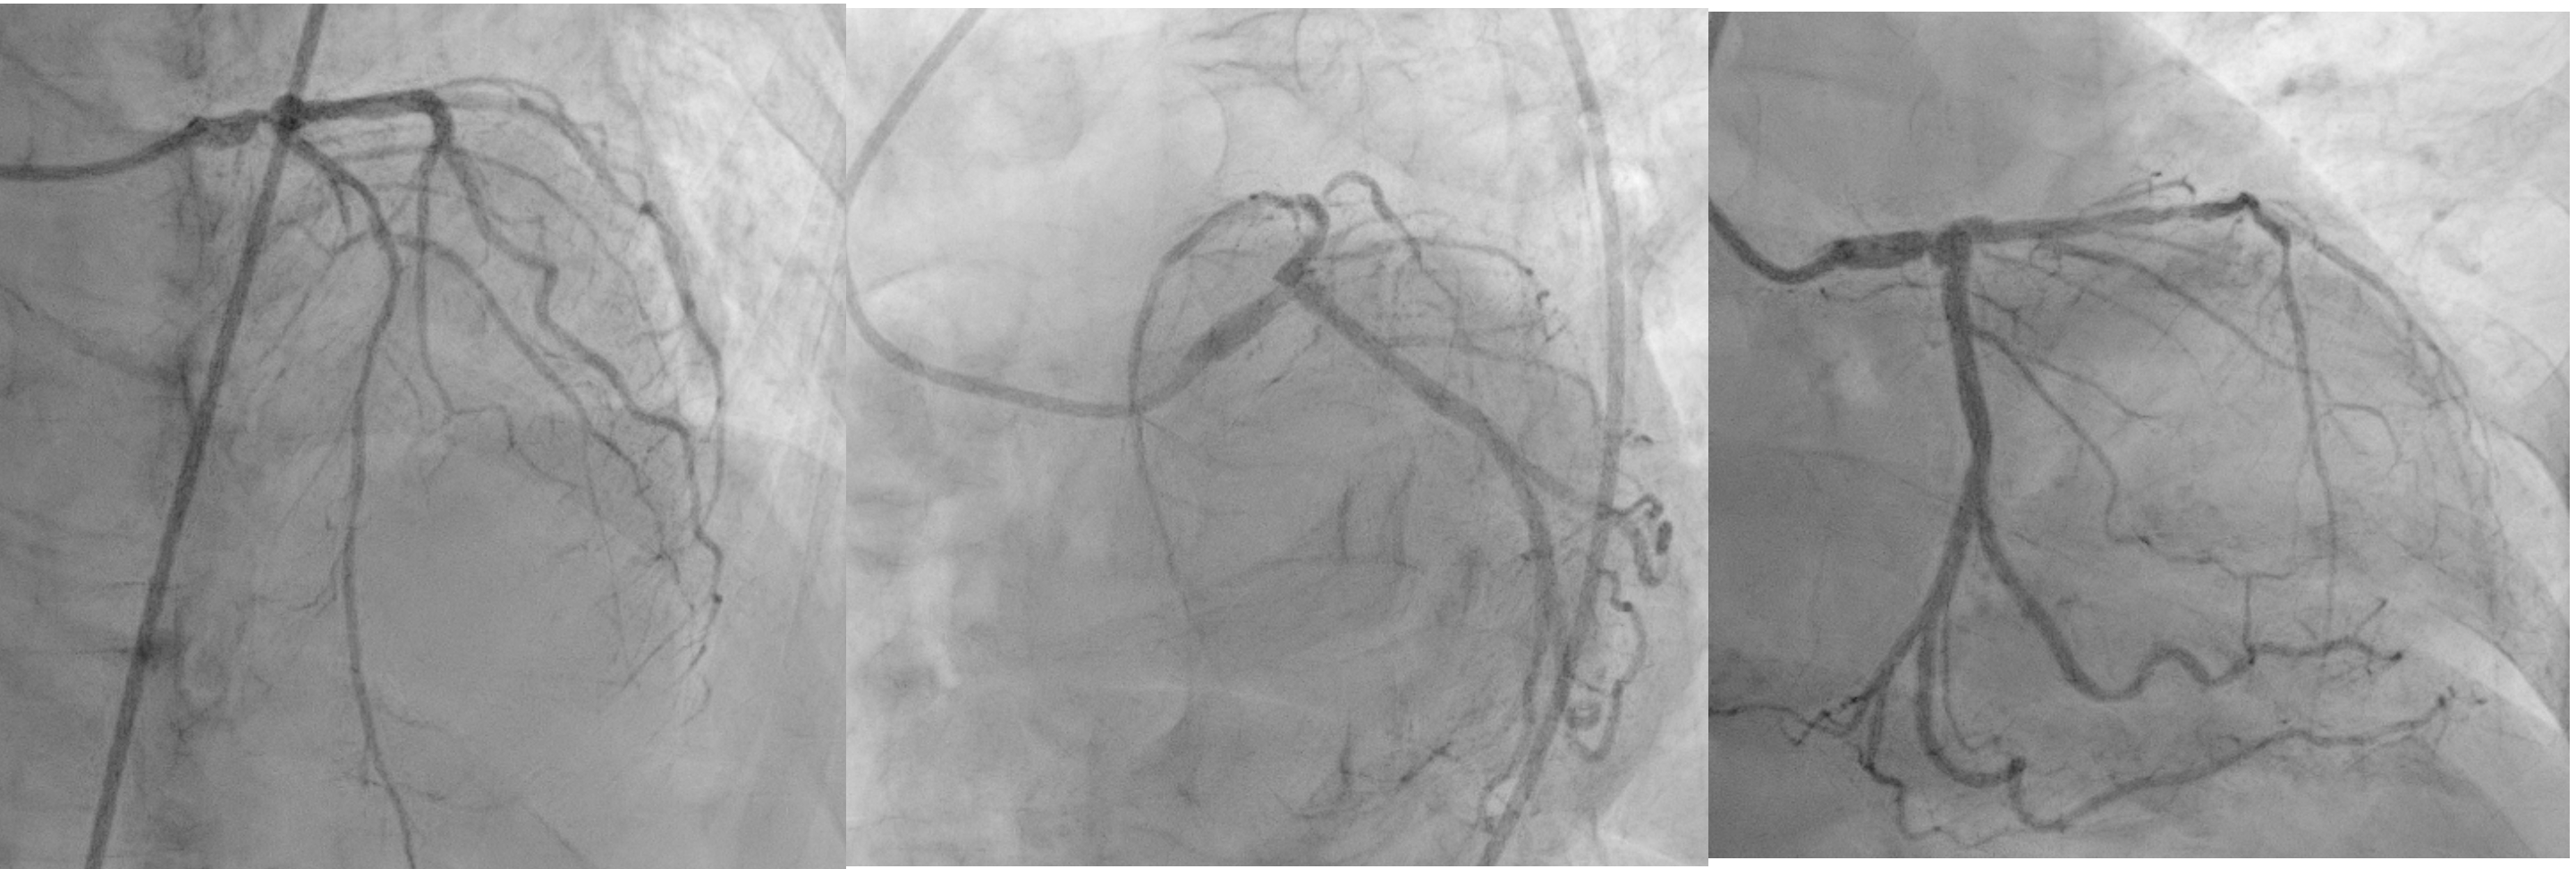

Relevant Catheterization Findings

Angiography showed 80% stenosis in the distal LM, with diffuse disease in LAD and a maximum 85% stenosis in the mid-LAD. There was a moderately calcified lesion extending from the distal LM to the proximal LAD. The LCx was normal, and the RCA had a 50% ostial stenosis. An IVUS catheter was advanced over a floppy wire showed a 270¡Æ calcified arc, 4 mm in length from the distal LM to the ostial LAD. The MLA of LM, osteal LAD and distal LAD consecutively was 3.25 mm©÷, 3.2 mm©÷ and 2.37 mm©÷